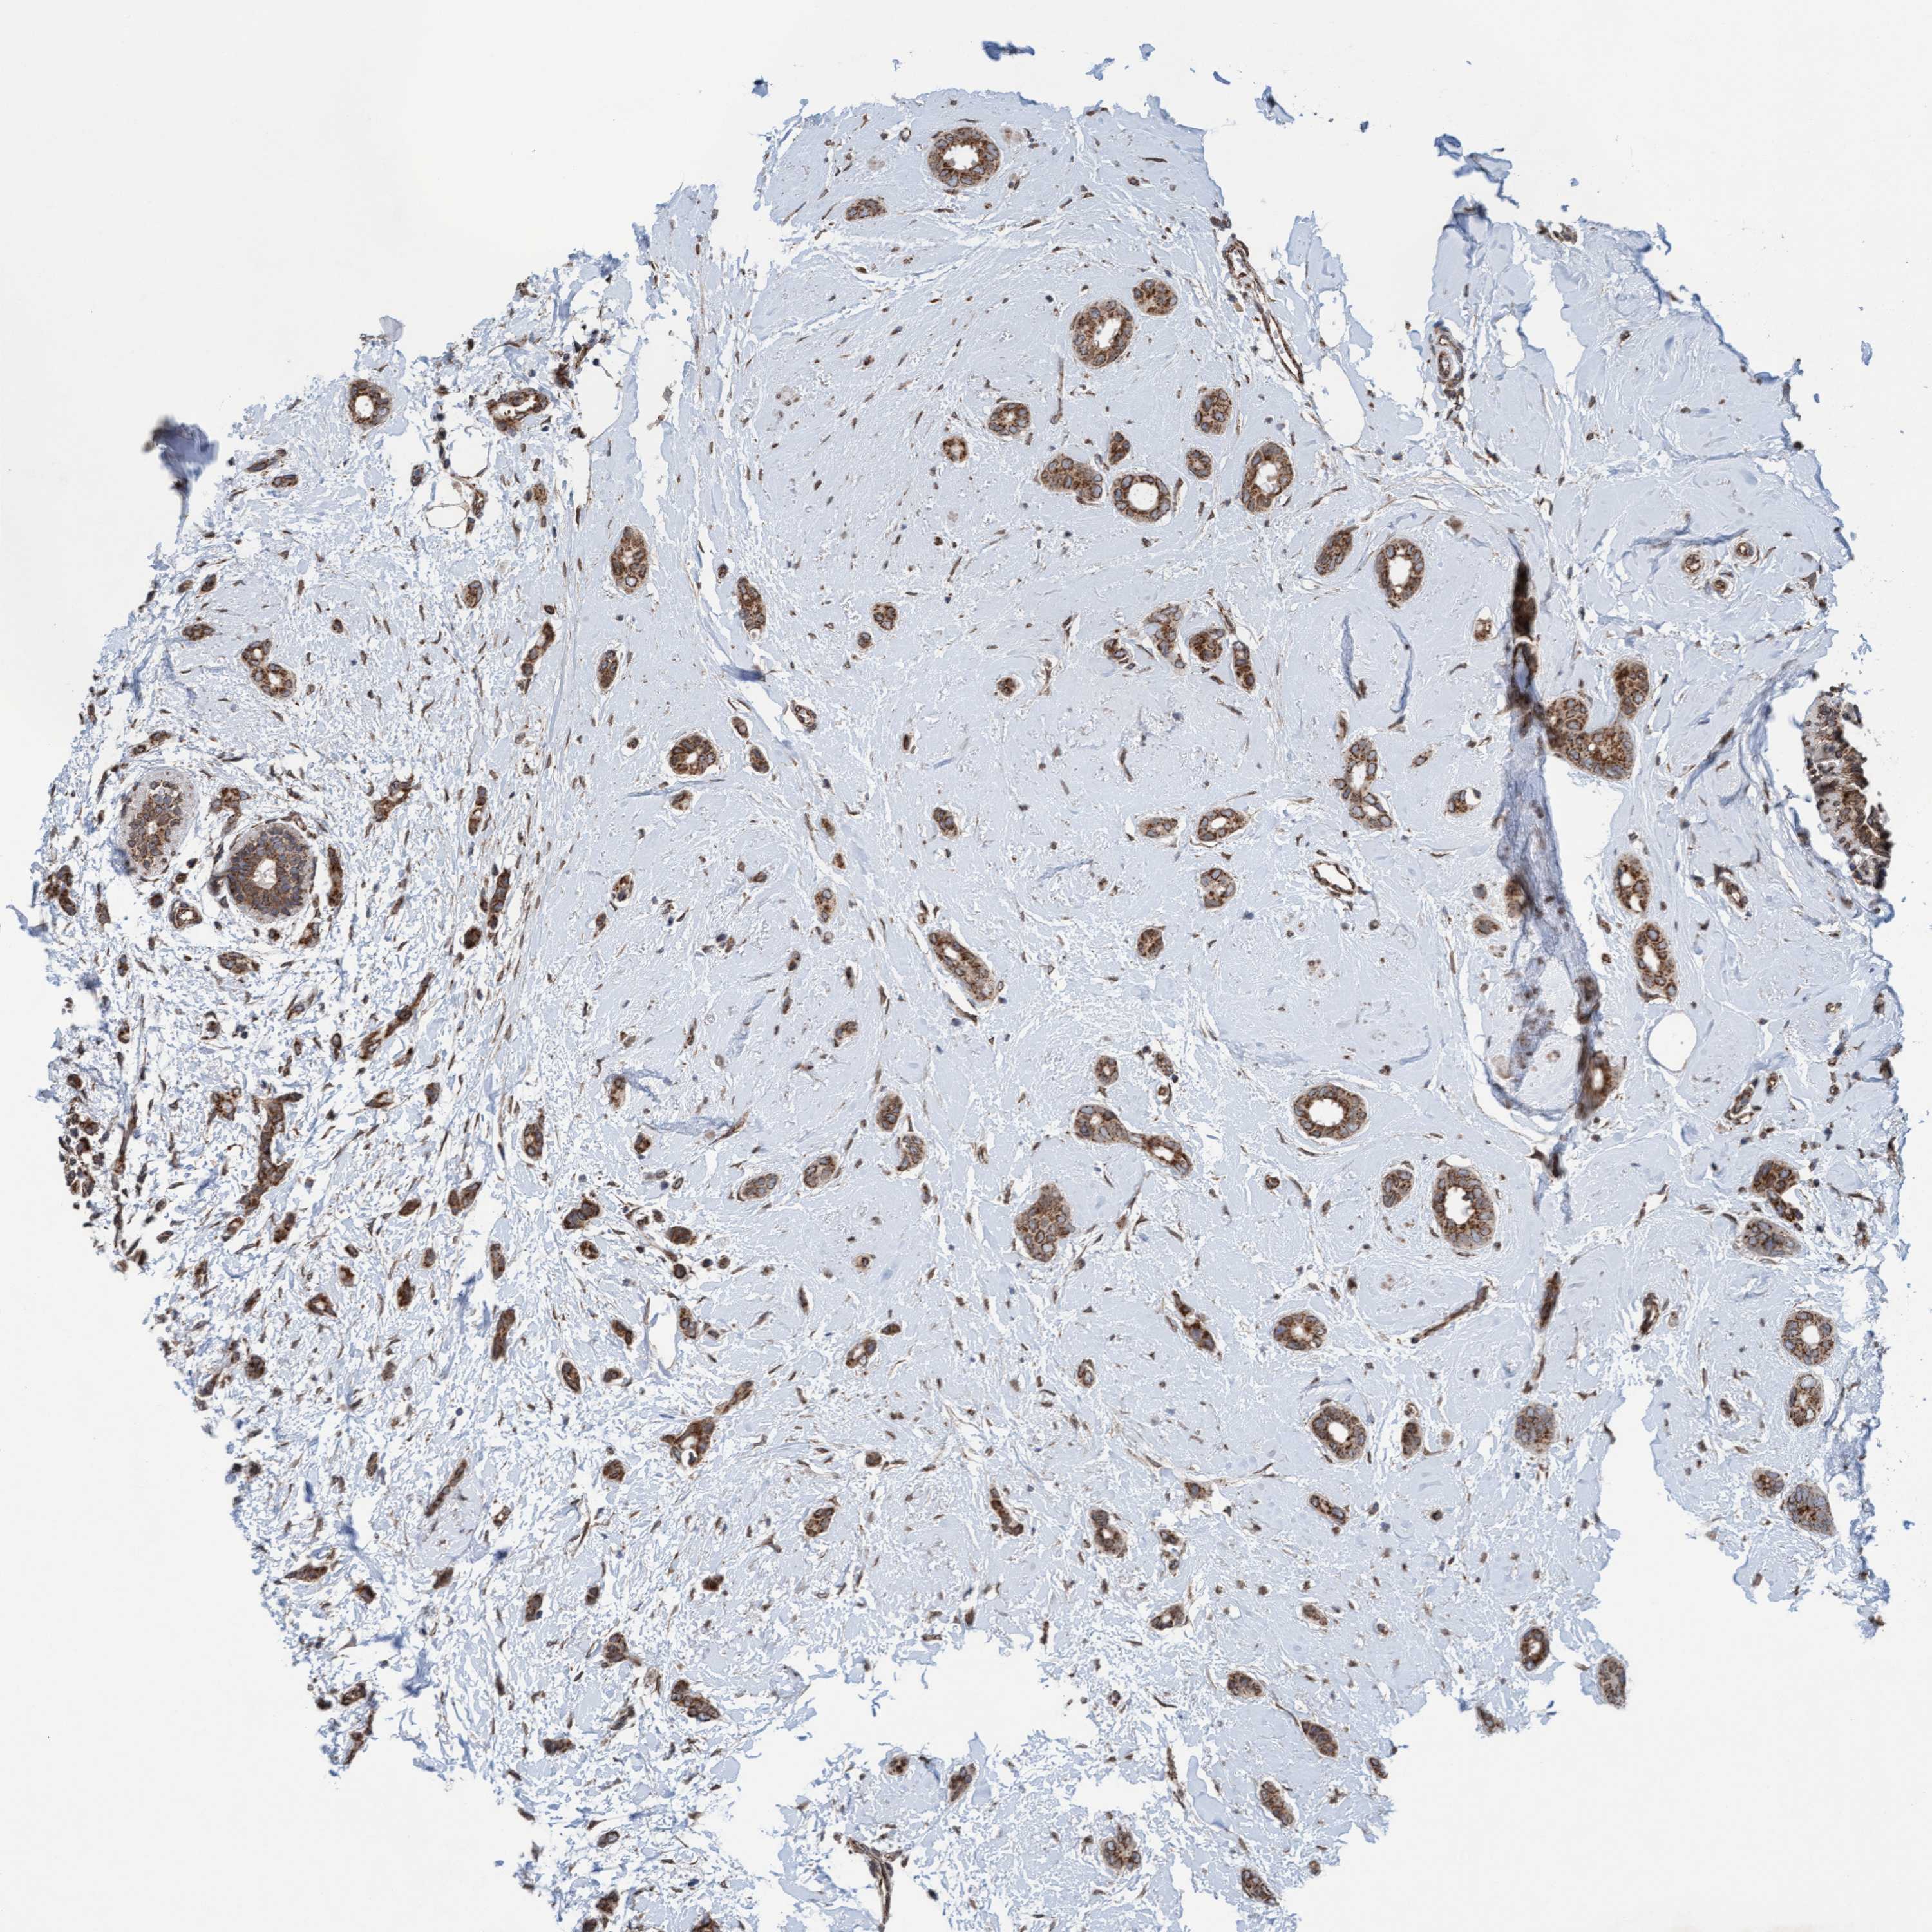

CANCER BREAST CANCER Show tissue menu

BRCA TCGA BRCA VALIDATION PROTEIN EXPRESSION